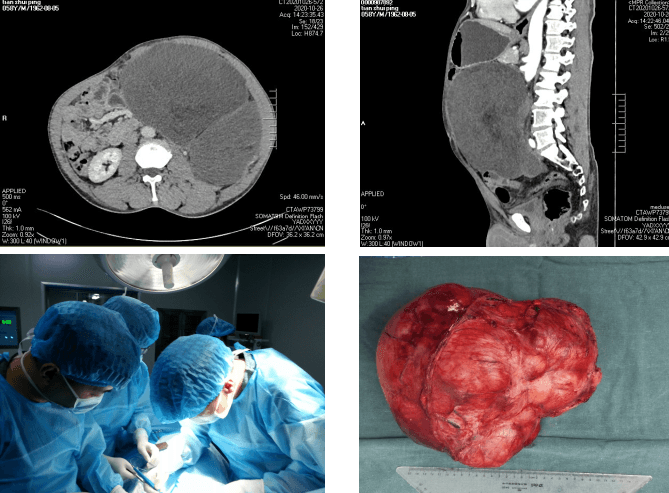

田某,男,50歲,因“腹脹6月余”入院。查體見腫瘤占據整個腹部,經影像學檢查,顯示腹部見一巨大軟組織腫塊影。苗主任對老人的身體進行仔細評估,術前檢查完善后,科室反復討論后,組織MDT多學科會診決定實施手術切除,并制定了詳細的手術方案及圍手術期應急預案。2020年5月22日上午,由苗滿園教授、李仁拴主治醫師等組成的手術團隊在全麻下為患者行“腹膜后巨大腫瘤切除術”。術中發現腫瘤位于腹膜后,約35cm×30cm×30cm,不規則型,實質性,占據左側腹腔空間,將腹腔內腸管等推擠至腹腔右側,左腎被擠壓至右上腹,右側輸尿管擴張。術中仔細分離,保護好腸系膜血管、腹主動脈、胰腺、脾臟、結腸等重要器官,在手術室的密切配合下,手術歷時3小時完成,切除腫瘤重達10kg。圍手術期嚴格執行ERAS流程,給予早期恢復飲食、術后第一天即可下床活動、多模式鎮痛等一系列治療措施,患者恢復順利,于術后10天治愈出院。術后病理提示腹膜后高分化脂肪肉瘤。

腹膜后腫瘤早期癥狀隱匿,常在生長至較大時出現癥狀被發現,但此時腫瘤常累及大血管、消化系統、泌尿生殖系統等重要臟器,腹膜后腫瘤手術平均出血約2000ml,止血困難,易導致出血死亡,手術切除難度極大。本次手術亮點:1. 術前多學科MDT、充分術前準備,將手術風險盡可能降至最低;2. 精湛的手術技巧幫助闖過手術關:術中精細解剖,避免損傷周圍臟器,完整切除了腹膜后巨大腫瘤;3. 個體化精準治療讓患者最大程度獲益。